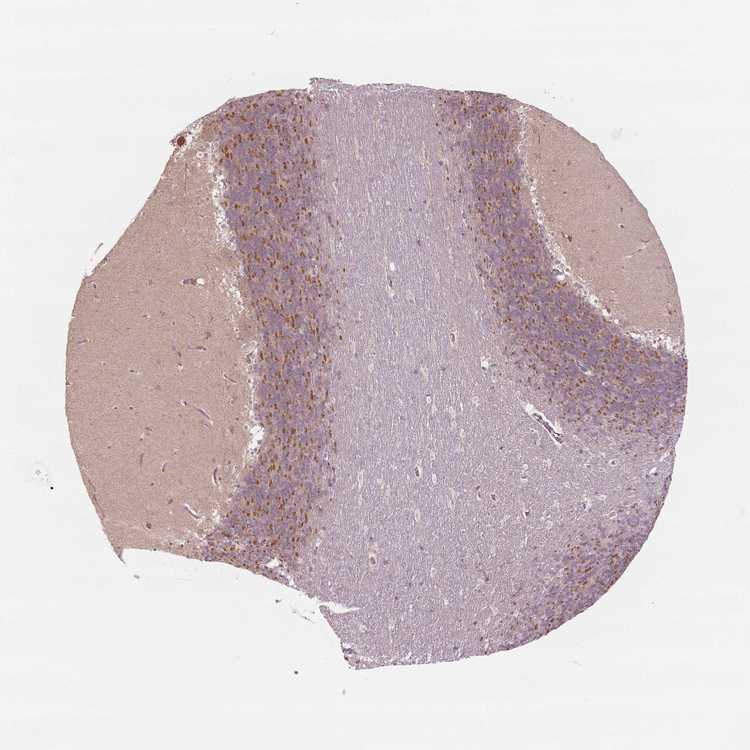

CEREBELLUM - Antibody stainingi

Antibody staining in the annotated cell types in the current human tissue is reported as not detected, low, medium, or high, based on conventional immunohistochemistry profiling in selected tissues. This score is based on the combination of the staining intensity and fraction of stained cells.

Each image is clickable and will lead to virtual microscopy that enables deeper exploration of all samples and also displays staining intensity scores, fraction scores and subcellular localization as well as patient and tissue information for each sample.

Antibody HPA012066

Purkinje cells Low

Cells in granular layer Medium

Cells in molecular layer Not detected